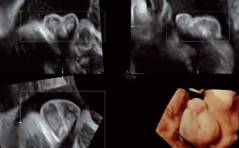

Der Transport durch den Eileiter: Wie funktioniert er eigentlich?

Und: Eine mögliche Erklärung für die Entstehung einer Eileiterschwan-gerschaft? / Ovarialkarzinom bei einem Transgender-Mann: Ein komple-xer Fall / FGM/FGC in der Schweiz – wie hoch ist die ...